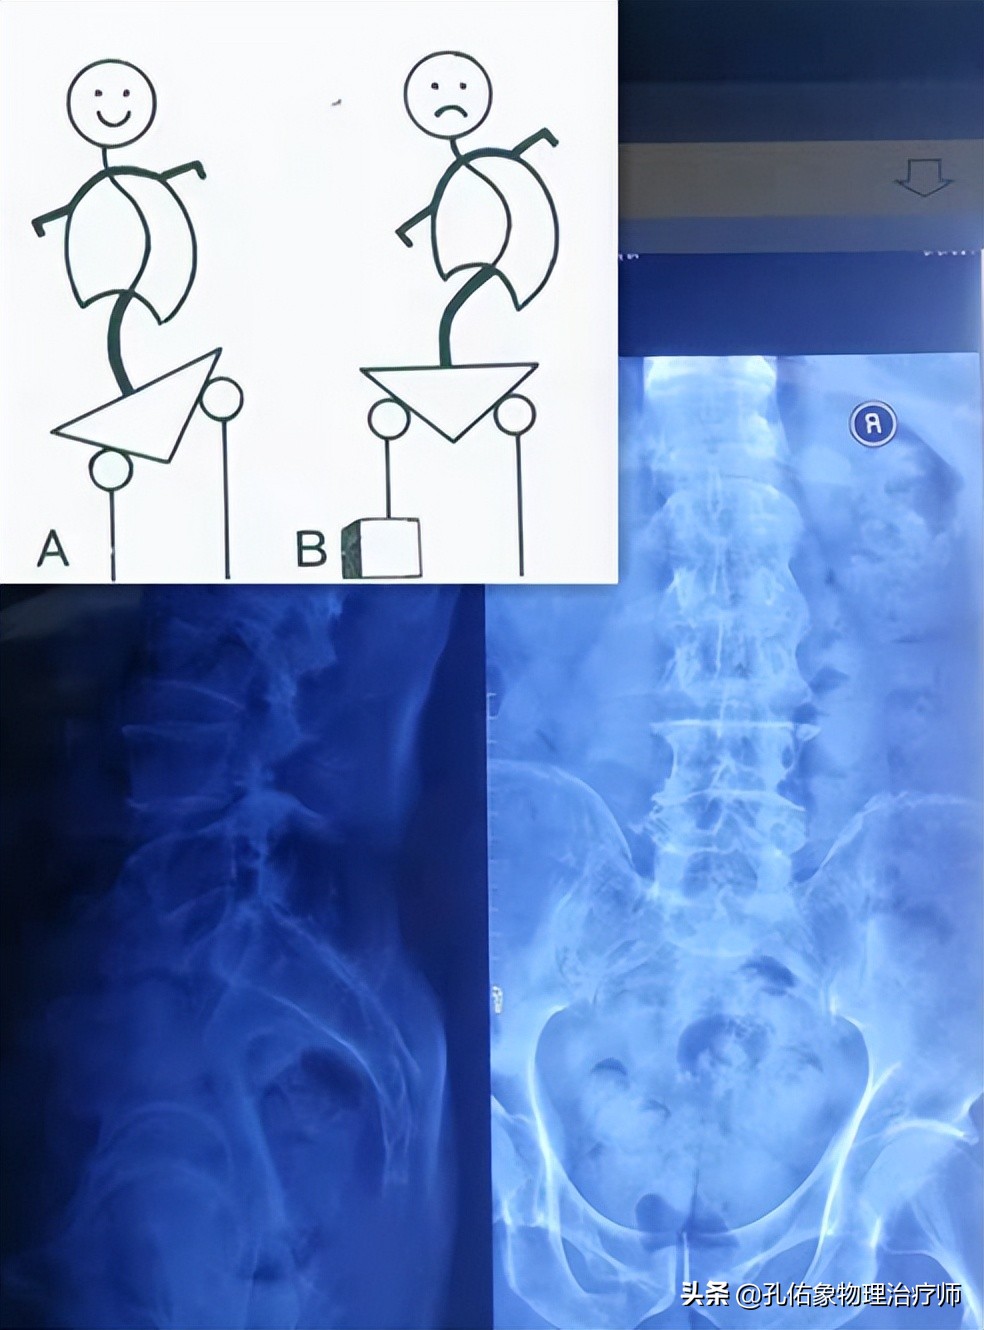

让其拍了一张腰、骨盆X片,结果是下图所示的样子:

阅片提示:腰4椎体相对腰5椎体后下移位,并有旋转;脊柱右侧弯;左右骨盆不等高,右侧骶髂关节钙化。